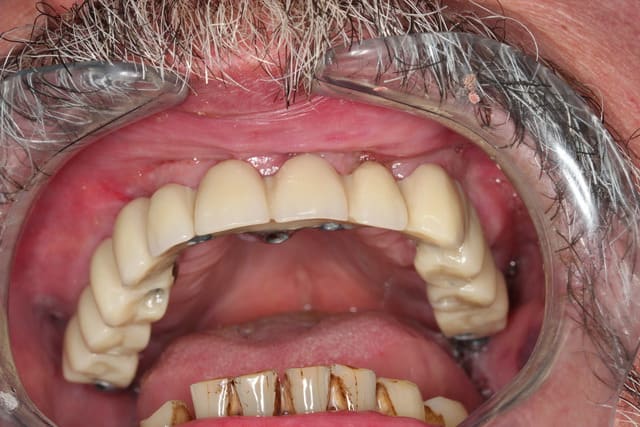

Et voilà ce ne fut pas facile mais c est fait

Tjs plus content de l avoir fait que de la voir à faire LOL

30/09/2013 à 18h18

Euh oui je sais le détartrage du bas n a pas été fait mais vu l urgence le travail en haut primait largement

Opéré mardi matin

Posé samedi matin